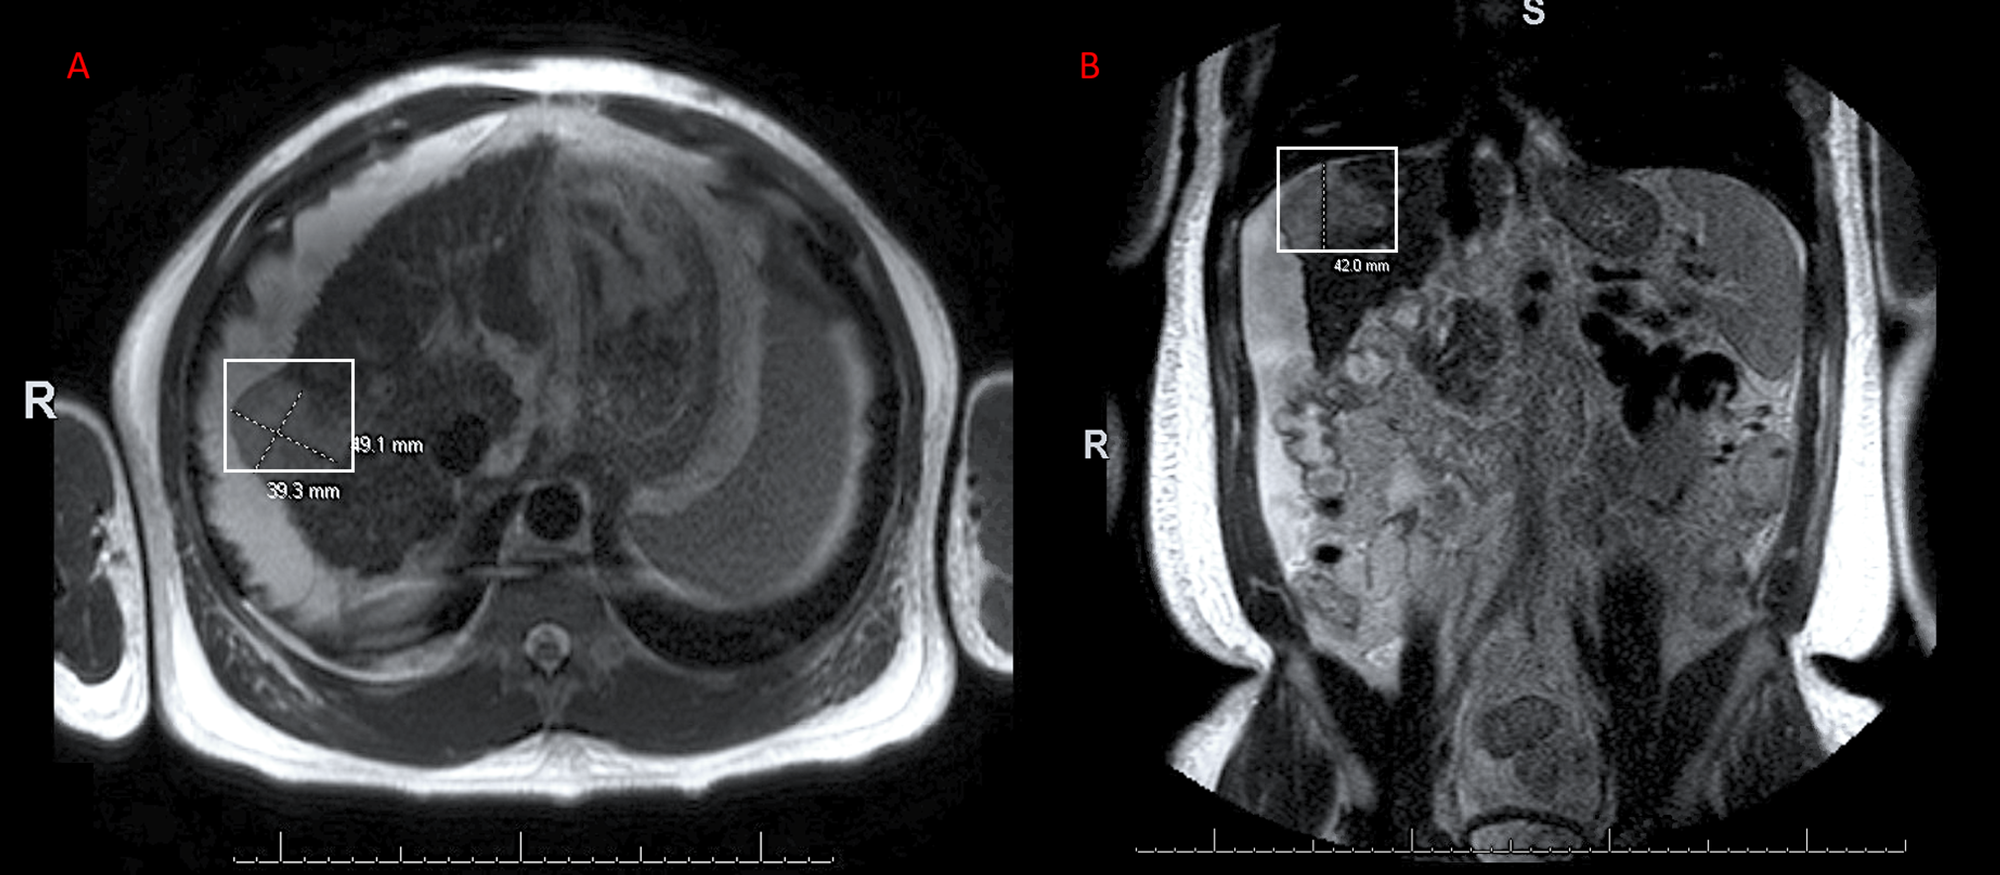

66yearold woman with cirrhosis secondary to autoimmune hepatitis and Autoimmune Hepatitis Mri To exclude other possibilities of chronic hepatitis. Depending on the degree of liver injury, lab values may indicate depressed liver function (e.g. Assessing the degree of inflammatory activity such as interface and lobular inflammation, which is not. To retrospectively evaluate the morphologic and enhancement features of the liver on magnetic. Autoimmune hepatitis (aih) is a chronic inflammatory disease of the. Autoimmune Hepatitis Mri.

MRI shows chronic hepatitis associated with hepatolithiasis (white Autoimmune Hepatitis Mri To exclude other possibilities of chronic hepatitis. How do doctors diagnose autoimmune hepatitis? Depending on the degree of liver injury, lab values may indicate depressed liver function (e.g. The role of imaging in a patient with possible autoimmune hepatitis is threefold: Ct and mri scans can look at your liver in more detail. Read more about scans and imaging tests. Autoimmune Hepatitis Mri.